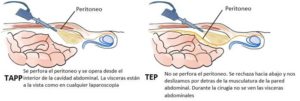

Ya desde hace unos pocos lustros, se ha observado que la cirugía mínimamente invasiva también puede ser usada para el tratamiento quirúrgico de la hernia inguinal. Hay 2 variedades de cirugía mínimamente invasiva de la hernia. La que se entra completamente en la cavidad abdominal (TAPP o laparoscópica) y la que nos deslizamos por detrás de la musculatura del abdomen sin llegar a entrar en la cavidad abdominal porque, la última capa, el peritoneo, queda indemne (TEP o endoscópica). Ambas tienen similares resultados, aunque con distintas peculiaridades en sus ventajas o inconvenientes que hacen más aconsejables una u otra según las circunstancias que rodean al paciente.

Ya desde hace unos pocos lustros, se ha observado que la cirugía mínimamente invasiva también puede ser usada para el tratamiento quirúrgico de la hernia inguinal. Hay 2 variedades de cirugía mínimamente invasiva de la hernia. La que se entra completamente en la cavidad abdominal (TAPP o laparoscópica) y la que nos deslizamos por detrás de la musculatura del abdomen sin llegar a entrar en la cavidad abdominal porque, la última capa, el peritoneo, queda indemne (TEP o endoscópica). Ambas tienen similares resultados, aunque con distintas peculiaridades en sus ventajas o inconvenientes que hacen más aconsejables una u otra según las circunstancias que rodean al paciente.